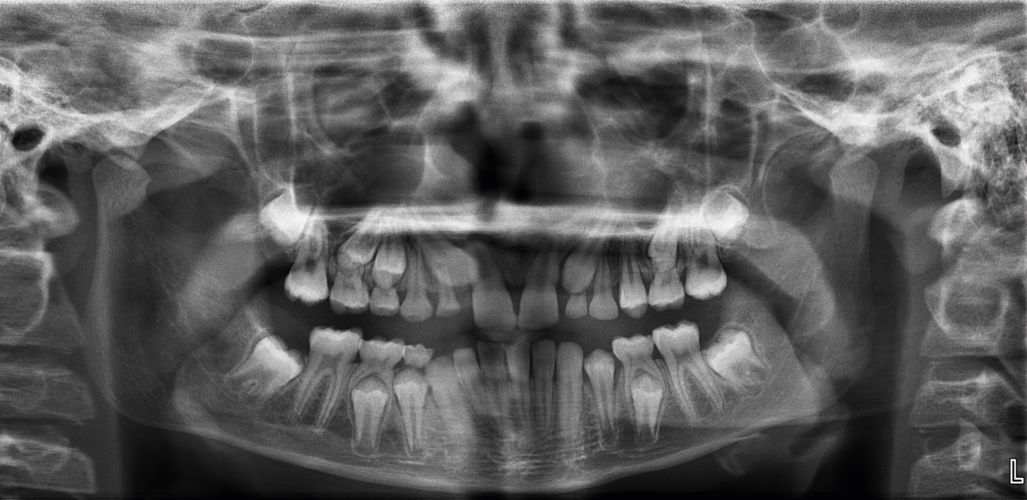

Question: S1 AM 1.7 Using the case history and the print of radiograph NB1_b, answer the following question on the answer score sheet. (Select ONE or MORE correct answers.) Which of the following is the most likely anatomical structure/diagnosis for the radiographic entity/entities?